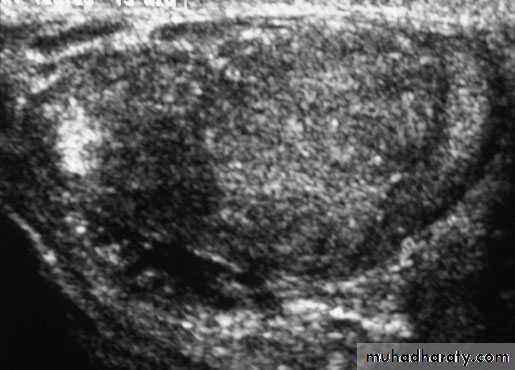

TORSION OF THE TESTIS ( Torsion of spermatic cord)

Rotation of the testis around the vertical axis of the cordIt is time limited due to arterial obstruction & the patient might lose his testis by ischemia (gangrene) if the diagnosis is delayed (6 hours).

Most common between 10 and 25 years of ageSudden agonizing pain in the groin and the lower abdomen.

The testis lie transversely high and the tender twisted cord can be palpated above it.

Doppler ultrasound scan will confirm the absence of the blood supply to the affected testisTreatment